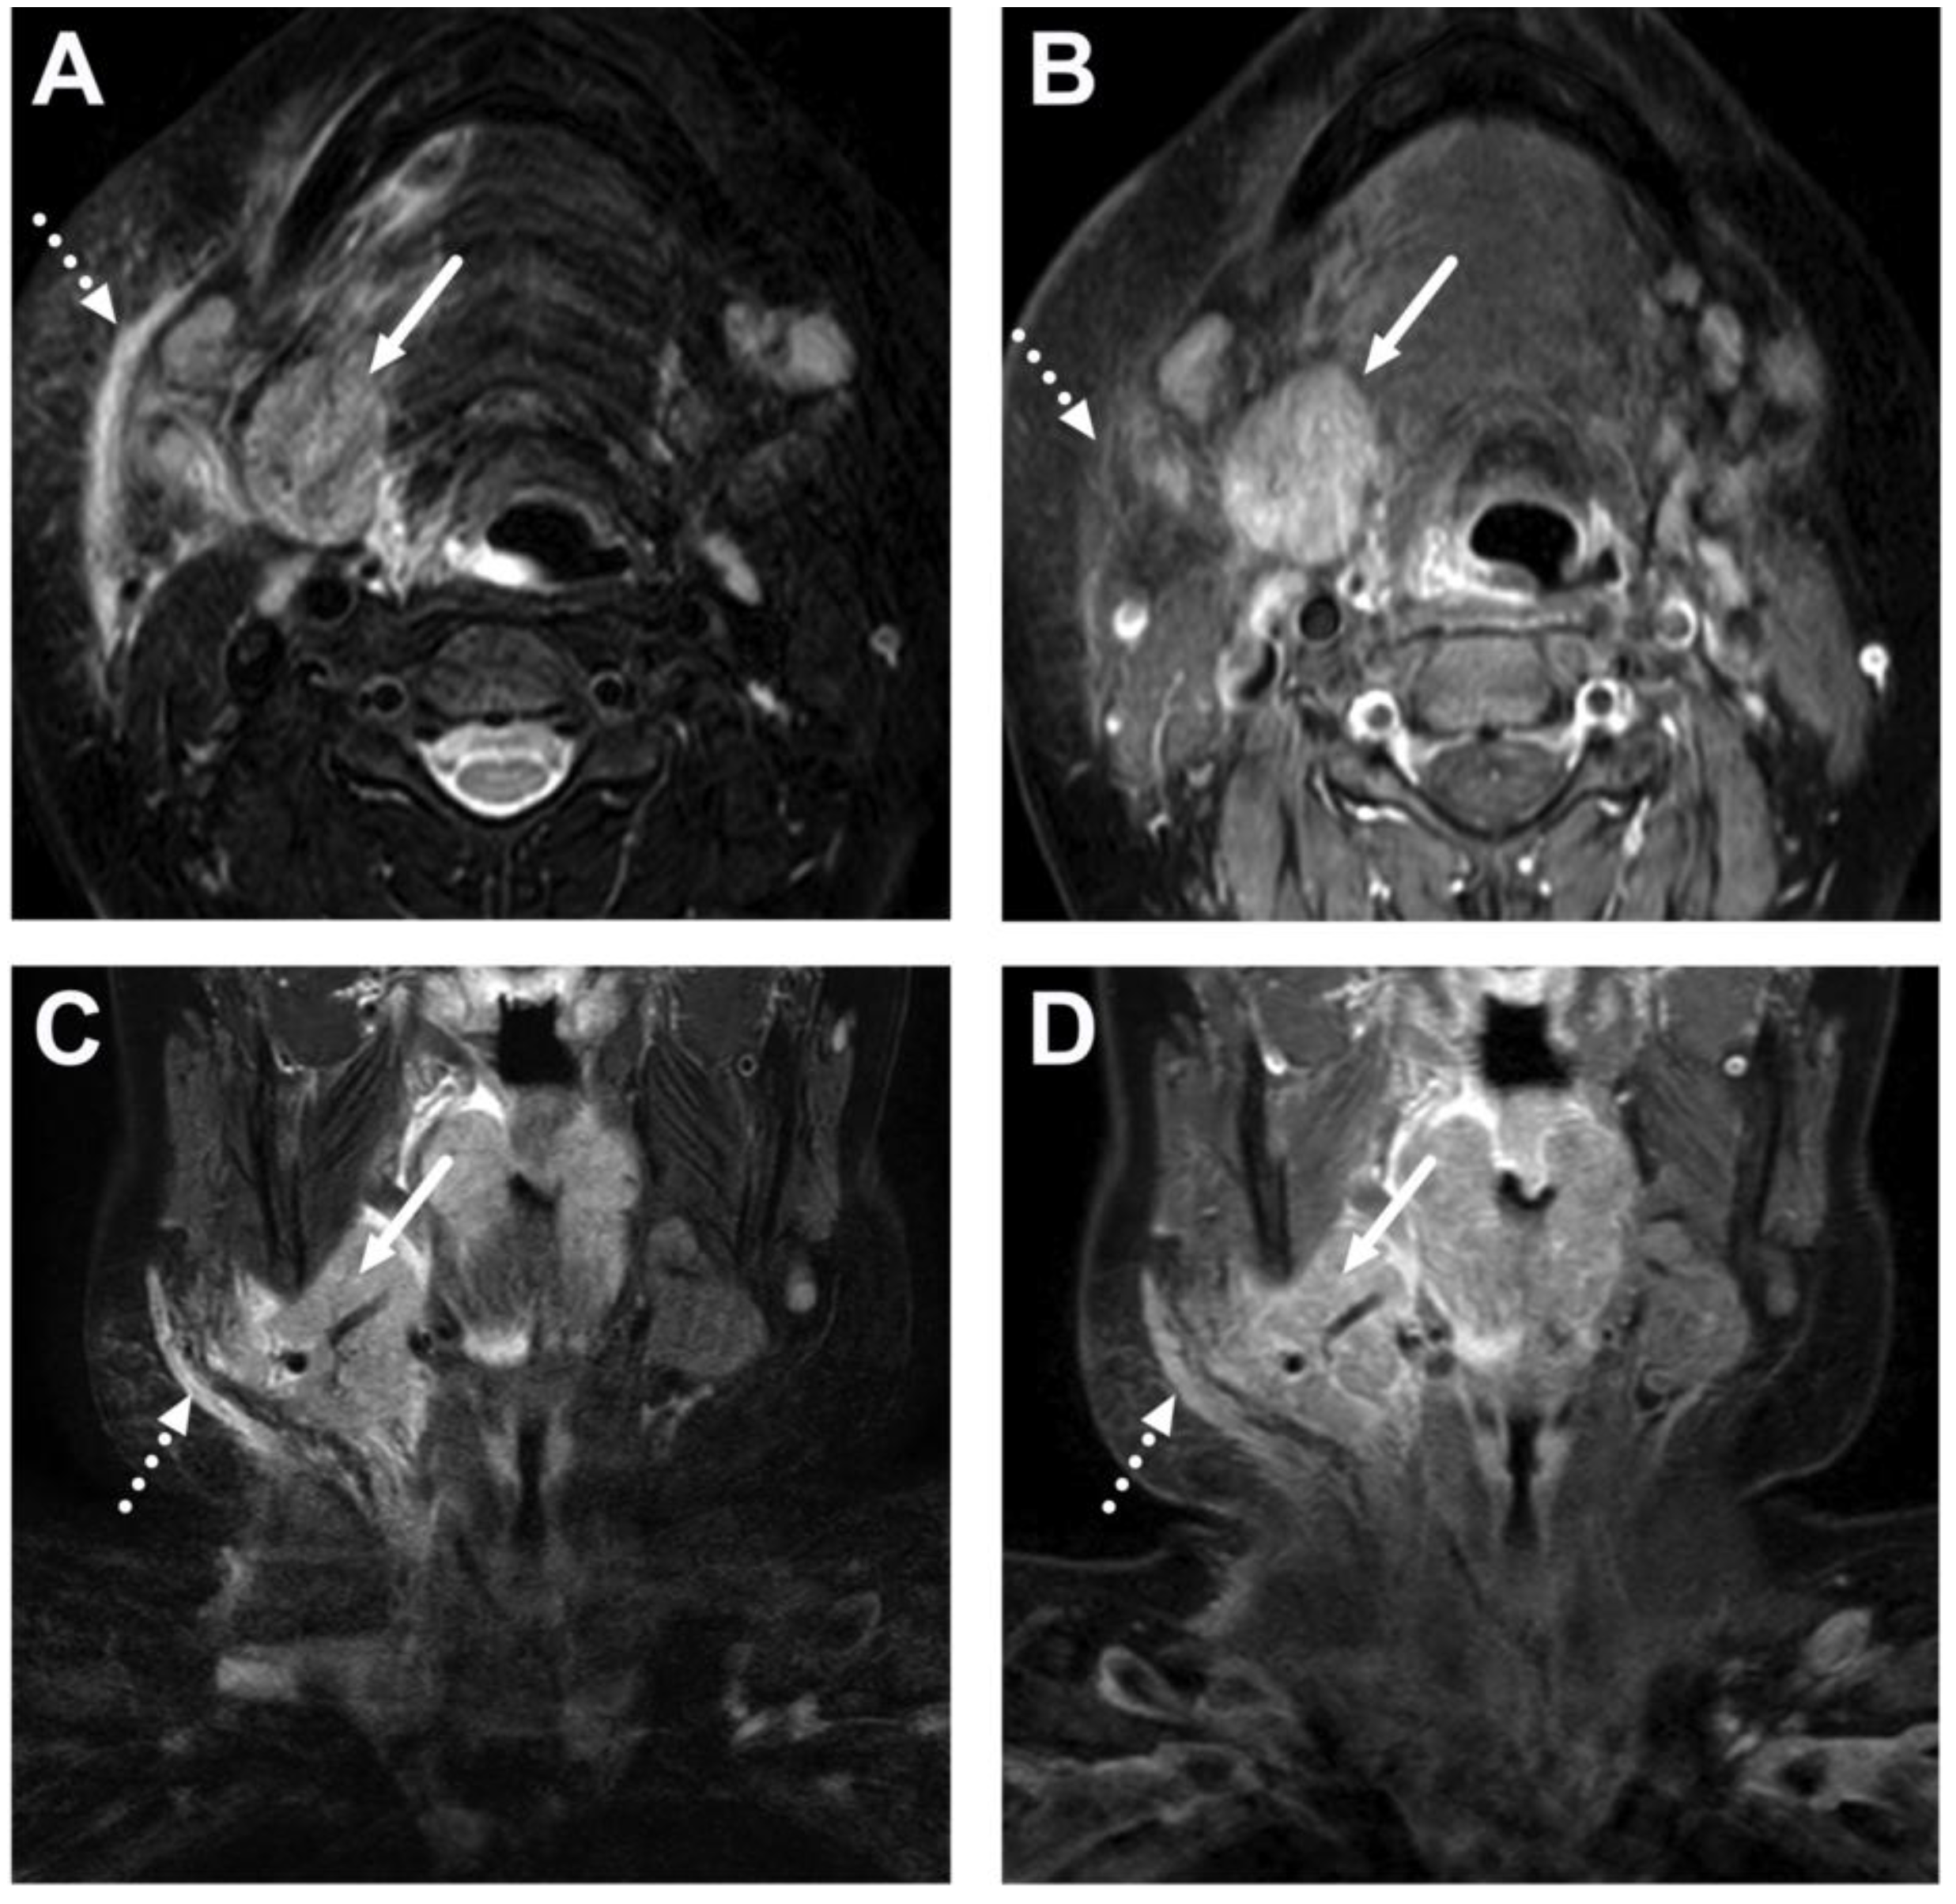

6. Complications

6.2. Venous Thrombosis

- George, E.; Callen, A.L.; Glastonbury, C.M. Atypical thrombophlebitis patterns in head and neck infections. Neuroradiol. J. 2023. [Google Scholar] [CrossRef]

| Abscess | T1 SE T2 Dixon (water) DWI post-contrast T1 Dixon (water) | Non-enhancing collection with low ADC values enclosed in abnormally enhancing soft tissue edema. | Detection of an abscess usually requires operative consideration and exact abscess location, and extensions are useful in operative planning. | Abscesses may have an intermediate T2 signal content; blood products and/or postoperative status may complicate abscess assessment; necrotic lymph nodes may be misinterpreted as suppurative lymphadenitis. |

| Complications | Whole protocol | Abscess extending to multiple deep neck spaces, mediastinis, venous thrombosis, and airway compromise. | Detection of potentially life-threatening conditions. | Magnetic resonance angiography (MRA) or CECT may be needed to diagnose venous thrombosis; defining airway compromise is difficult. |